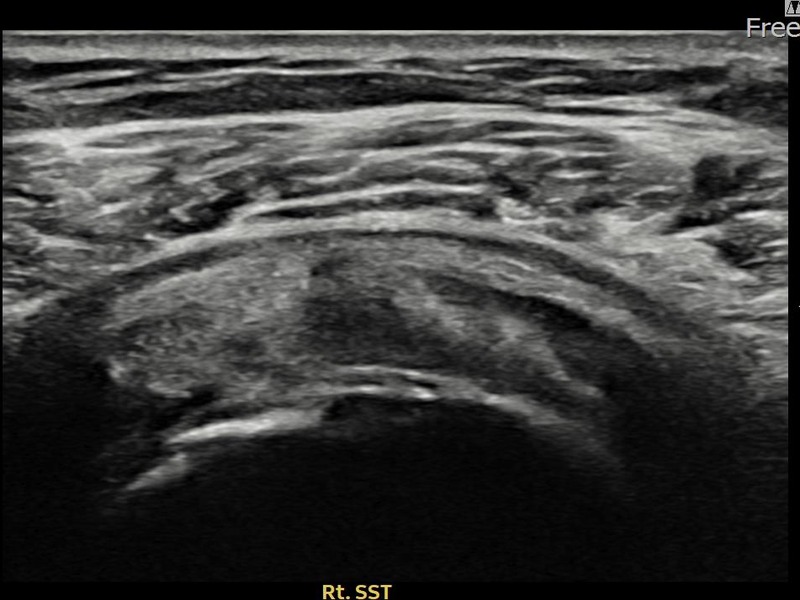

최ㅇㅇ님 · 우측 극상근건 관절면측 파열 진행형

우측 어깨 파열이 진행된 상태로 수술 없이 치료를 원해 내원하셨습니다. 다각도 초음파 평가 후 축소봉합술을 시행하여 힘줄 구조가 안정화되었습니다.

상세 보기 →